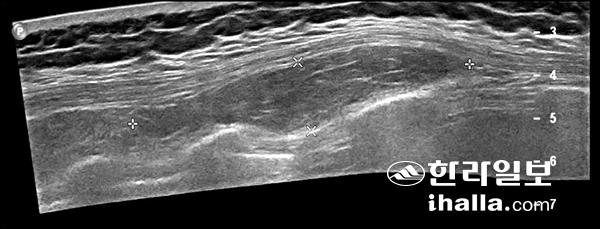

등부위의 초음파 검사로 발견한 지방종이다.

다음으로 근육 및 피하지방과 같은 연부조직에 생기는 각종 종양을 발견하고 진단할 수 있다. 대표적으로 표피포함낭, 결절종과, 지방종과 같은 양성 종양들이 있으며 이런 양성 종양 같은 경우 초음파 검사 시행만으로 필요시 제거할 수 있다. 물론 악성 종양이 의심되거나, 제거하려는 종양 주위로 혈관, 신경등의 중요 구조물이 지나간다면 안전한 제거를 위해 CT나 MRI 등의 보다 자세한 검사가 필요할 수 있다. 하지만 근골격계 초음파 검사를 통해 쉽게 검사할 수 있는 경우 비용과 시간 등을 절약할 수 있어 큰 장점이 있다.